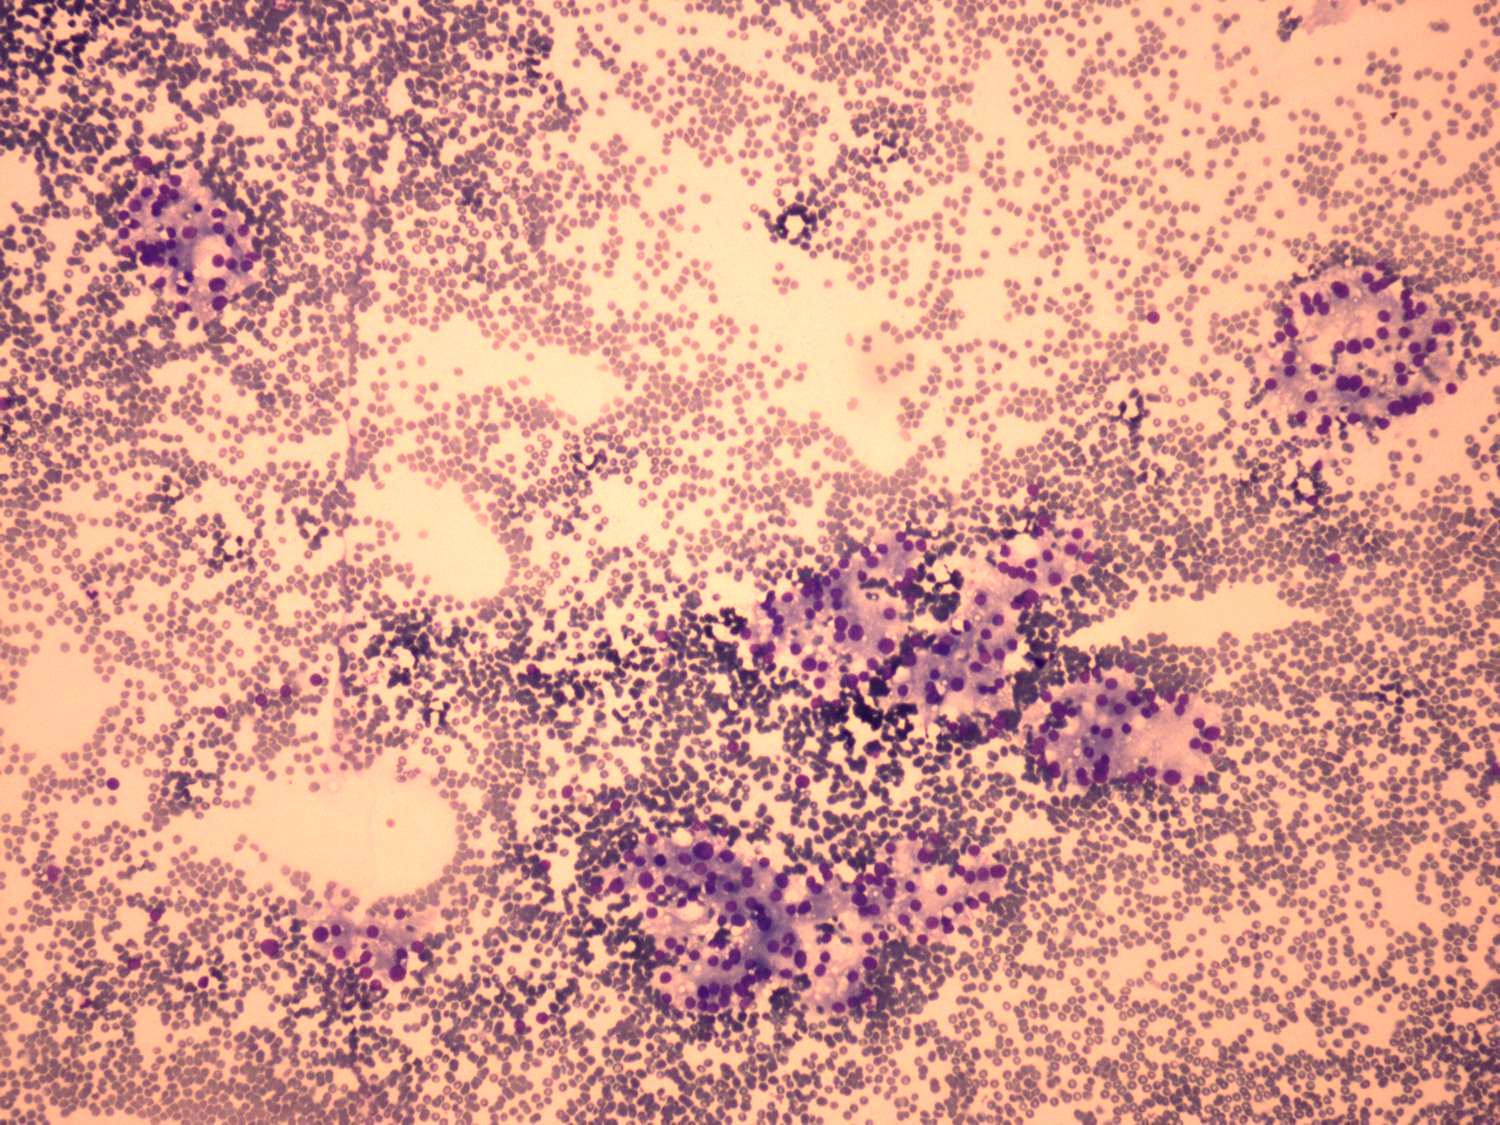

Graves' disease - case 1191 (cytologic picture 1)

Wright-Giemsa staining, 100x.   There is no colloid in the background. Follicular cells are located in normo- and microfollicles.